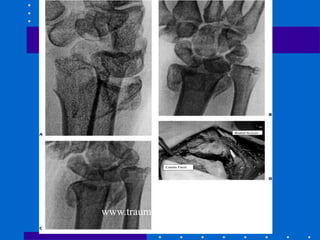

• Fraturas expostas são tipicamente palmar e

ulnar, tendo em vista que rádio desloca

dorsal e extremidade da ulna expõe palmar.